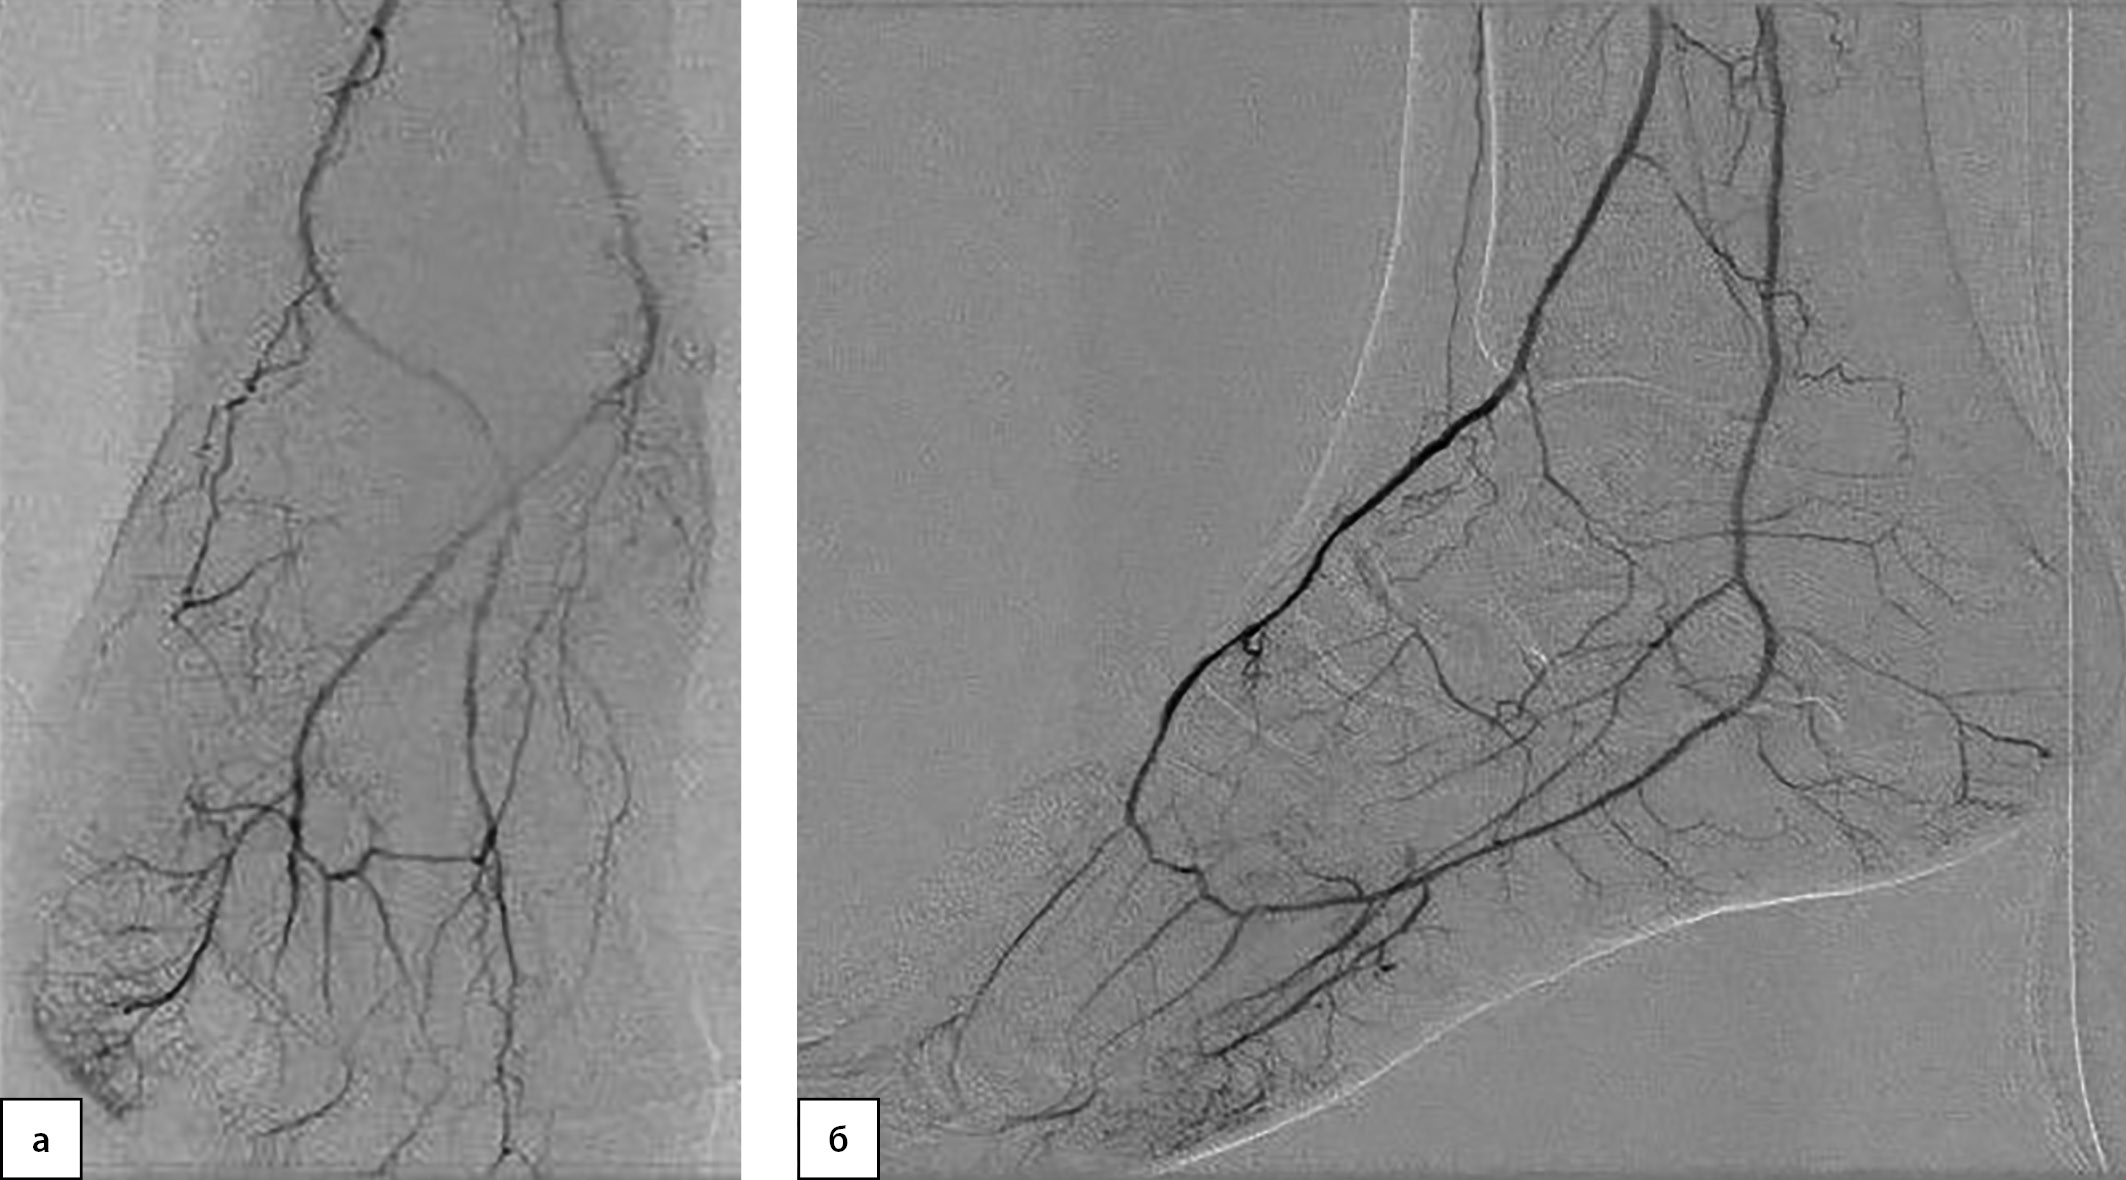

Рисунок 5. Интраоперационная рентгеноконтрастная ангиография

до механической реканализации и баллонной ангиопластики в боковой проекции

(медленное и слабое заполнение контрастом артерий. стопы), боковая проекция.

После реваскуляризации правой нижней конечности восстановлен магистральный кровоток в стопе по МБА, заполняющей ТАС, ЗББА (рис. 6а, 6б).

Рисунок 6. Рентгеноконтрастная ангиография артерий правой нижней конечности

до и после реваскуляризации.

а — контрольная рентгеноконтрастная ангиография после механической реканализации и баллонной ангиопластики в прямой проекции (оптимальная визуализация артерий стопы);

б — контрольная рентгеноконтрастная ангиография после механической реканализации и баллонной ангиопластики в боковой проекции (оптимальная визуализация артерий стопы).